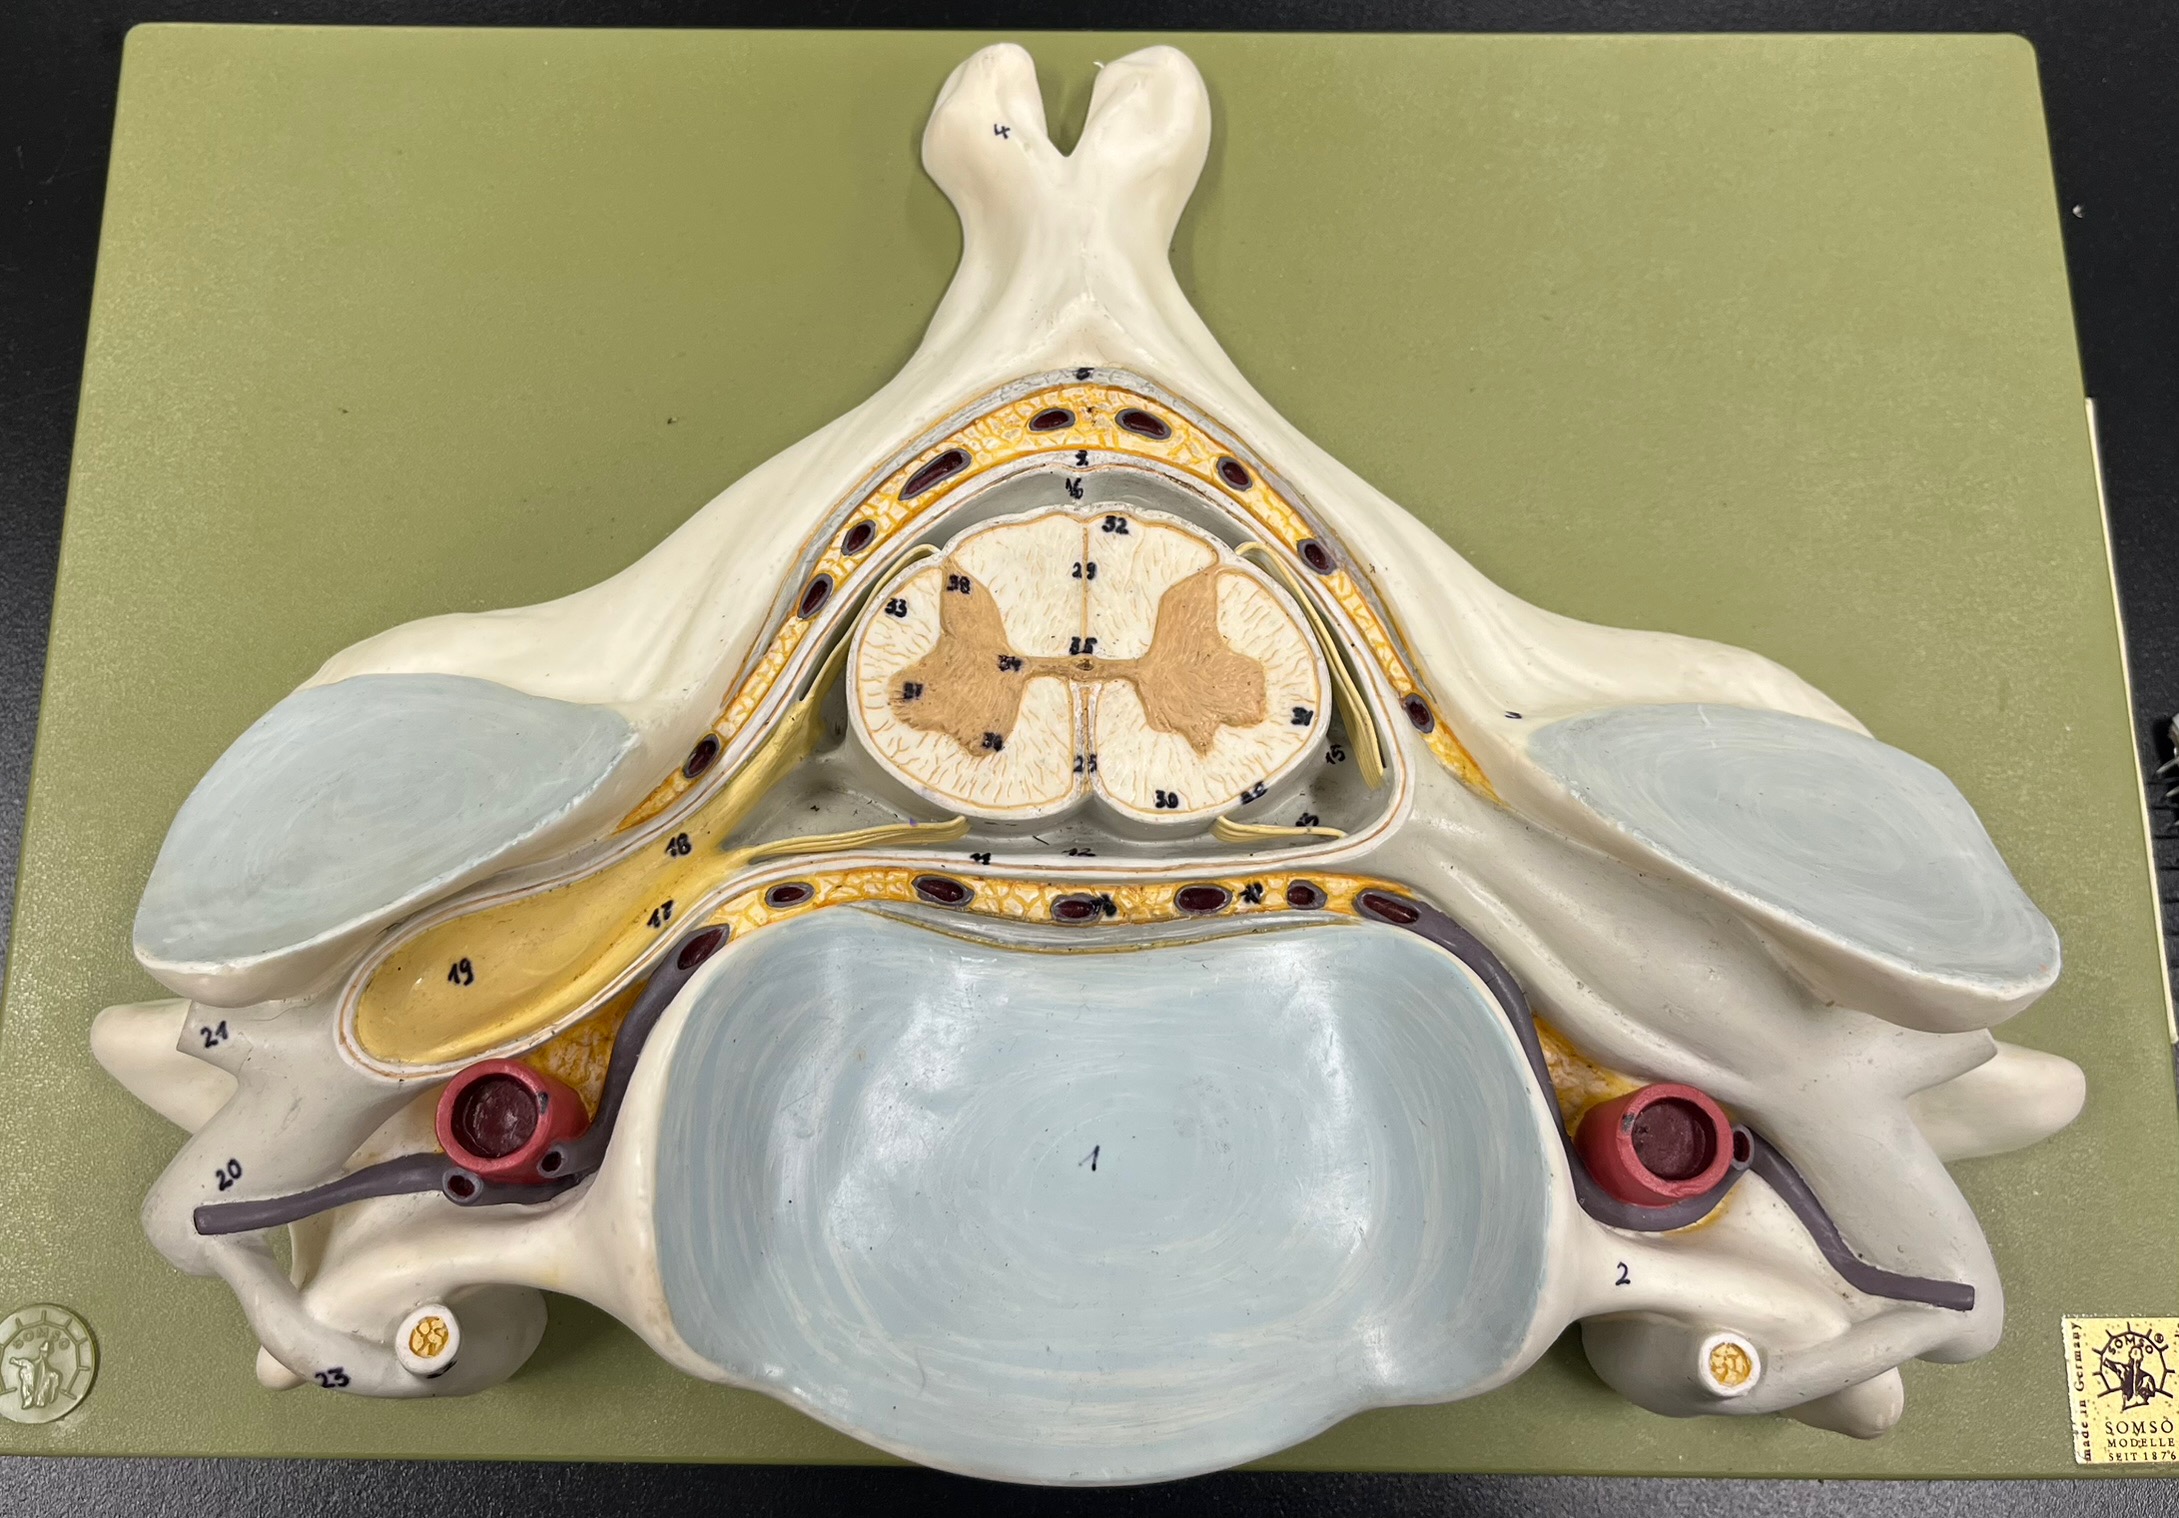

epidural space

dura mater

subdural space

arachnoid mater

subarachnoid space

pia mater

denticulate ligaments

What is the groove here?

anterior median fissure

posterior median sulcus

posterior (dorsal) horn

posterior (dorsal) horn; R—>L

anterior (ventral) horn

lateral horn (selected models)

gray commissure

central canal

anterior column

lateral column

posterior column

white commissure

posterior (dorsal) root ganglion

What is the bulb here?

posterior (dorsal) root ganglion

posterior (dorsal) root

posterior (dorsal) root

anterior (ventral) root

anterior (ventral) root

dorsal ramus

dorsal ramus

ventral ramus

ventral ramus

rami communicantes

rami communicantes

sympathetic chain ganglia

sympathetic chain ganglia